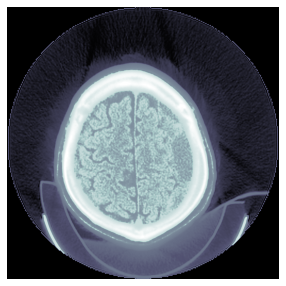

(0008, 0018) SOP Instance UID UI: ID_e0cc6a4b5

(0008, 0060) Modality CS: 'CT'

(0020, 0032) Image Position (Patient) DS: [-125.000, -122.268, 115.936]

(0020, 0037) Image Orientation (Patient) DS: [1.000000, 0.000000, 0.000000, 0.000000, 0.978148, -0.207912]